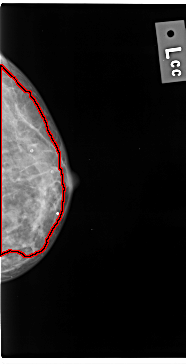

C_0039_1.LEFT_CC

FILE: C_0039_1.LEFT_CC.OVERLAY

TOTAL_ABNORMALITIES 1

ABNORMALITY 1

LESION_TYPE CALCIFICATION TYPE AMORPHOUS DISTRIBUTION DIFFUSELY_SCATTERED

ASSESSMENT 3

SUBTLETY 4

PATHOLOGY MALIGNANT

TOTAL_OUTLINES 1

BOUNDARY